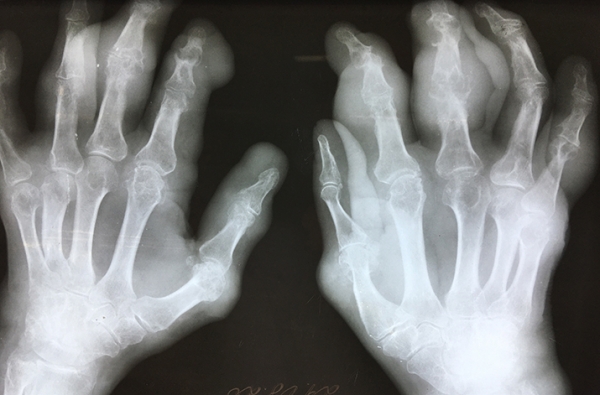

Фото носит иллюстративный характер. Из открытых источников.

Характерная клиника начальной подагры не вызывает сомнений в диагнозе. Трудности в диагностике возникают при первичном обращении пациентов с многолетней подагрой, а также при атипичном поражении суставов. Многолетняя подагра характеризуется множественным поражением суставов, упорным, длительным течением, маскируется под другие болезни суставов. За свою долгую практику довелось наблюдать подагрическое поражение сухожилий и пяток, фасеточных суставов позвоночника, грудино-ключичных сочленений, плечевых суставов.

В сложных диагностических случаях помогает нахождение подагрических тофусов, которые могут быть размером от нескольких миллиметров до невероятно огромных. Подагрические тофусы — это по сути склады мочевой кислоты, куда она собирается при избытке в крови. Чаще всего тофусы появляются над суставами, в частности, в области локтевых суставов, нередко на ушных раковинах.

Работая со множеством пациентов, я наблюдал самые разные случаи образования тофусов, как редкие, так и типичные. Многие из них фотографировал и могу поделиться частью снимков (см. фото).

Фото предоставлены Я. Евко.